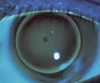

What condition is this ?

Keratoconus